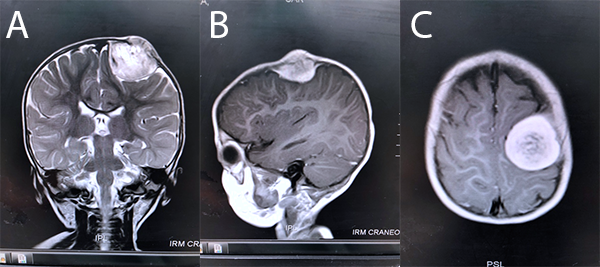

Se trata de paciente femenino lactante de 1 año de edad, que es valorada en Hospital de Salud Pública, por presentar tumoración a nivel del cuero cabelludo, por lo que es llevada a la consulta de dermatología, en donde se valora que no hubo pérdida de folículo piloso -alopecia-, sin cambios de coloración de la piel, ni descamación. A la maniobra de pilotracción no hubo positividad para fragilidad pilosa. Se descarta forunculosis del cuero cabelludo. Con sospecha de probable quiste epidermoide, fue referido a neurocirugía pediátrica en Hospital de Niños “Dr. Roberto Gilbert” donde se completaron estudios imagenológicos (figura 1). La exploración neurológica fue normal. Se decide realizar exéresis de la lesión, la cual se logra de forma completa (figura 2).

Figura 1: RM de encéfalo en donde se puede apreciar en a) secuencia ponderada T2 coronal, lesión ocupante de espacio extra-intracraneal en región frontal izquierda, hiperintensa, homogónea, de bordes bien definidos, con un mayor componente intracraneal, b) secuencia ponderada T1 contrastada sagital y c) secuencia ponderada T1 contrastada axial, en donde se puede observar el efecto de masa sobre el cerebro subyacente.